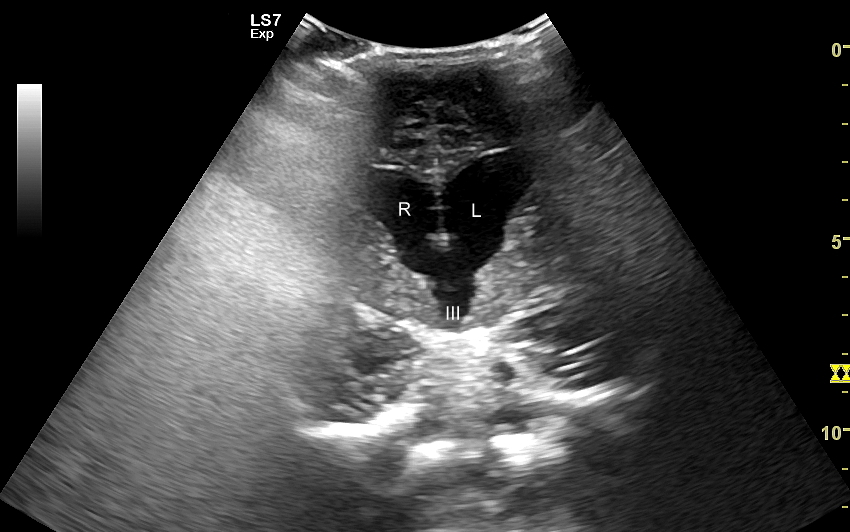

USG główki to podstawowa metoda diagnostyczna mózgu i struktur okołomózgowych u wcześniaków, noworodków i niemowląt. Badanie jest bezbolesne i nieryzykowne w porównaniu do rezonansu magnetycznego, podczas którego dziecko poddawane jest znieczuleniu ogólnemu. Przeprowadzenie szerokiego i szczegółowego badania USG główki jest możliwe aż do momentu zarośnięcia ciemiączka, czyli chrzęstnej struktury w pokrywie czaszki. Ze względu na cienką kość skroniową czaszki dziecka w późniejszym okresie możliwa jest wciąż częściowa ocena mózgowia w badaniu USG. Ambulatoryjne badanie USG przezciemiączkowe zwykle zalecane jest przez neonatologa, pediatrę lub neurologa dziecięcego w celu oceny mózgu wcześniaków, dzieci z małą masą urodzeniową, dzieci po epizodzie niedotlenienia lub krwawienia wewnątrzczaszkowego w trakcie porodu lub okresu noworodkowego, a także w przypadku wystąpienia drgawek, podejrzenia wady układu nerwowego, np. wodogłowia.

W USG główki dziecka oceniane są struktury wewnątrzczaszkowe, tj. mózg wraz z jego układem komór wewnętrznych, sploty naczyniówkowe, istota biała mózgu i obszary jąder podstawy mózgu, morfologia zakrętów i bruzd mózgowia, przestrzeń przymózgowa, a w trybach dopplerowskich wybrane naczynia tętnicze i żylne mózgu, w tym zatoki żylne. Oceniane są również cechy ciśnienia śródczaszkowego. W opisie badania podawane są również wymagane przez neurologa tzw. wskaźniki komorowe oraz wymiary wybranych struktur.

Badania USG mózgu dziecka wykonywane w warunkach szpitalnych i ambulatoryjnych różnią się od siebie charakterem stwierdzanych patologii. W szpitalu dominują ostre krwawienia wewnątrzczaszkowe oraz śródmózgowe. Z kolei najczęstszymi chorobami i stanami patologicznymi, które spotyka się w trakcie badania USG przezciemiączkowego przeprowadzanego w warunkach ambulatoryjnych są pozostałości po krwawieniach dokomorowych oraz śródmózgowych w postaci poszerzenia układu komorowego i torbieli; pozostałości po uszkodzeniach niedokrwiennych w postaci leukomalacji okołokomorowej i zaników mózgowych; poza tym zmiany pozapalne i wodogłowie wewnętrzne bądź zewnętrzne. Sporadycznie wykrywane są wady rozwojowe oraz guzy mózgu.

Badanie USG służy również ocenie dojrzałości mózgowia dziecka; otóż mózg wcześniaka różni się od mózgu starszego niemowlęcia. U tego pierwszego obserwuje się m. in. mniej zaawansowane bruzdowanie kory mózgowej oraz warianty rozwojowe, z których najczęstszym jest jama przegrody przezroczystej. Zaburzenia rozwoju kory mózgowej u płodu, a potem u niemowlęcia, obserwowane są w przypadku palenia papierosów przez ciężarną lub spożywania przez nią alkoholu, w przypadku powikłań przebiegu ciąży, a także powikłań okołoporodowych.